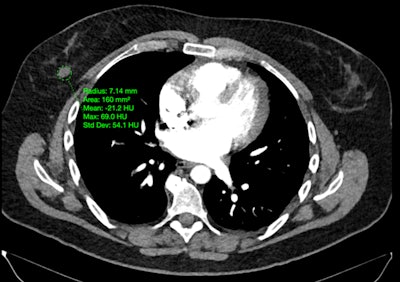

Projected Lifetime Cancer Risks From Current Computed Tomography Imaging. Smith-Bindman, et al, JAMA Internal Medicine, April 14, 2025. To learn more about this paper, click here.

The second finalist for Scientific Paper of the Year presented findings suggesting that cancers associated with radiation from CT scans could eventually account for 5% of all new cases annually. The fallout of the findings is included in the Minnies Most Significant News Event in Radiology category this year.

Led by Rebecca Smith-Bindman, MD, a group at the University of California, San Francisco developed a risk model based on approximately 93 million scans in 62 million patients in 2023.

The team found that approximately 103,000 radiation-induced cancers were projected to result from 93 million scans. Risks were higher in children and adolescents, yet higher CT use in adults accounted for most (93,000) radiation-induced cancers, the researchers reported.